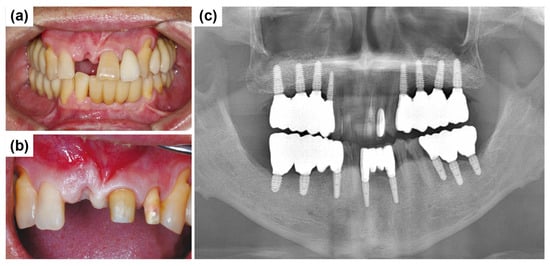

As ongoing maintenance, six-monthly follow-ups with dental plaque control were conducted. Additional periodontal treatment was provided as required. Annual panoramic radiographs were obtained to monitor implant prognosis. At the two-year follow-up, the implant prosthesis remained stable (Figure 15).

Figure 15.

Panoramic radiograph after 2 years.